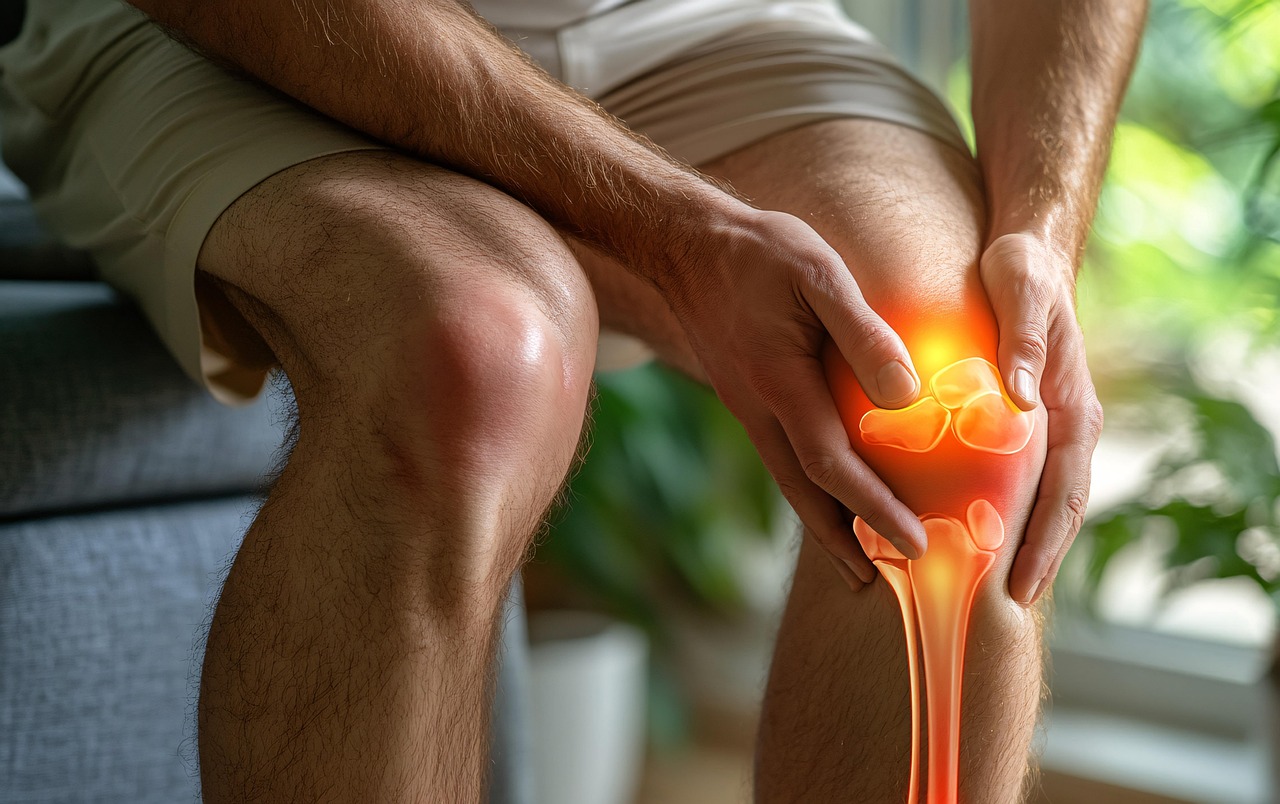

나이가 들면 무릎이나 허리 관절이 자주 아프고 움직임이 불편해지는 경우가 많습니다. 이런 불편을 방치하면 삶의 질이 크게 떨어질 수 있죠. 하지만 다행히 관절 건강을 지켜주는 성분이 있습니다. 바로 ‘콘드로이친’인데요.

콘드로이친(Chondroitin)은 우리 몸의 연골, 뼈, 인대 등에 존재하는 중요한 성분으로, 관절 건강을 유지하는 데 핵심적인 역할을 합니다. 특히 연골을 탄력 있고 건강하게 유지시켜 관절이 움직일 때 충격을 흡수하고 마찰을 줄여주는 기능을 합니다.